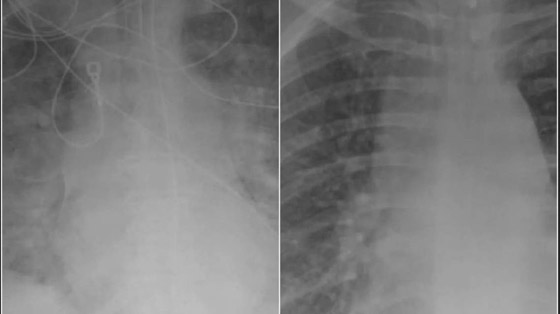

كشفت صور جديدة بالأشعة السينية عن الفرق الكبير بين رئتي الأشخاص الذين حصلوا على لقاح كورونا والذين لم يحصلوا على اللقاح.

تُظهر عمليات المسح التأثير الصادم لفيروس كورونا على الأعضاء الداخلية للمرضى، حيث قال الأطباء إن الأشخاص غير المطعمين هم من "يصابون بالمرض حقًا". وقال الدكتور سام دوراني من مركز دير فالي الطبي "الأشخاص الوحيدون الذين يمرضون حقًا هم الأشخاص غير المحصنين. وفي كثير من الأحيان يحتاجون إلى التهوية والأكسجين".

وأوضح الدكتور دوراني أن المرضى الذين تم تطعيمهم والذين أصيبوا بفيروس كورونا لديهم المزيد من الهواء المتدفق إلى رئتيهم، مع تلوين الجزء الأكبر من الرئتين باللون الأسود في الفحص، وهذا يعني أن هناك ضررًا ضئيلًا جدًا أو لا يوجد ضرر على الرئتين. وتظهر صورة الفحص من شخص غير محصن أن الرئتين محتقنتان للغاية، مما يحد من تدفق الأكسجين في جميع أنحاء الجسم.